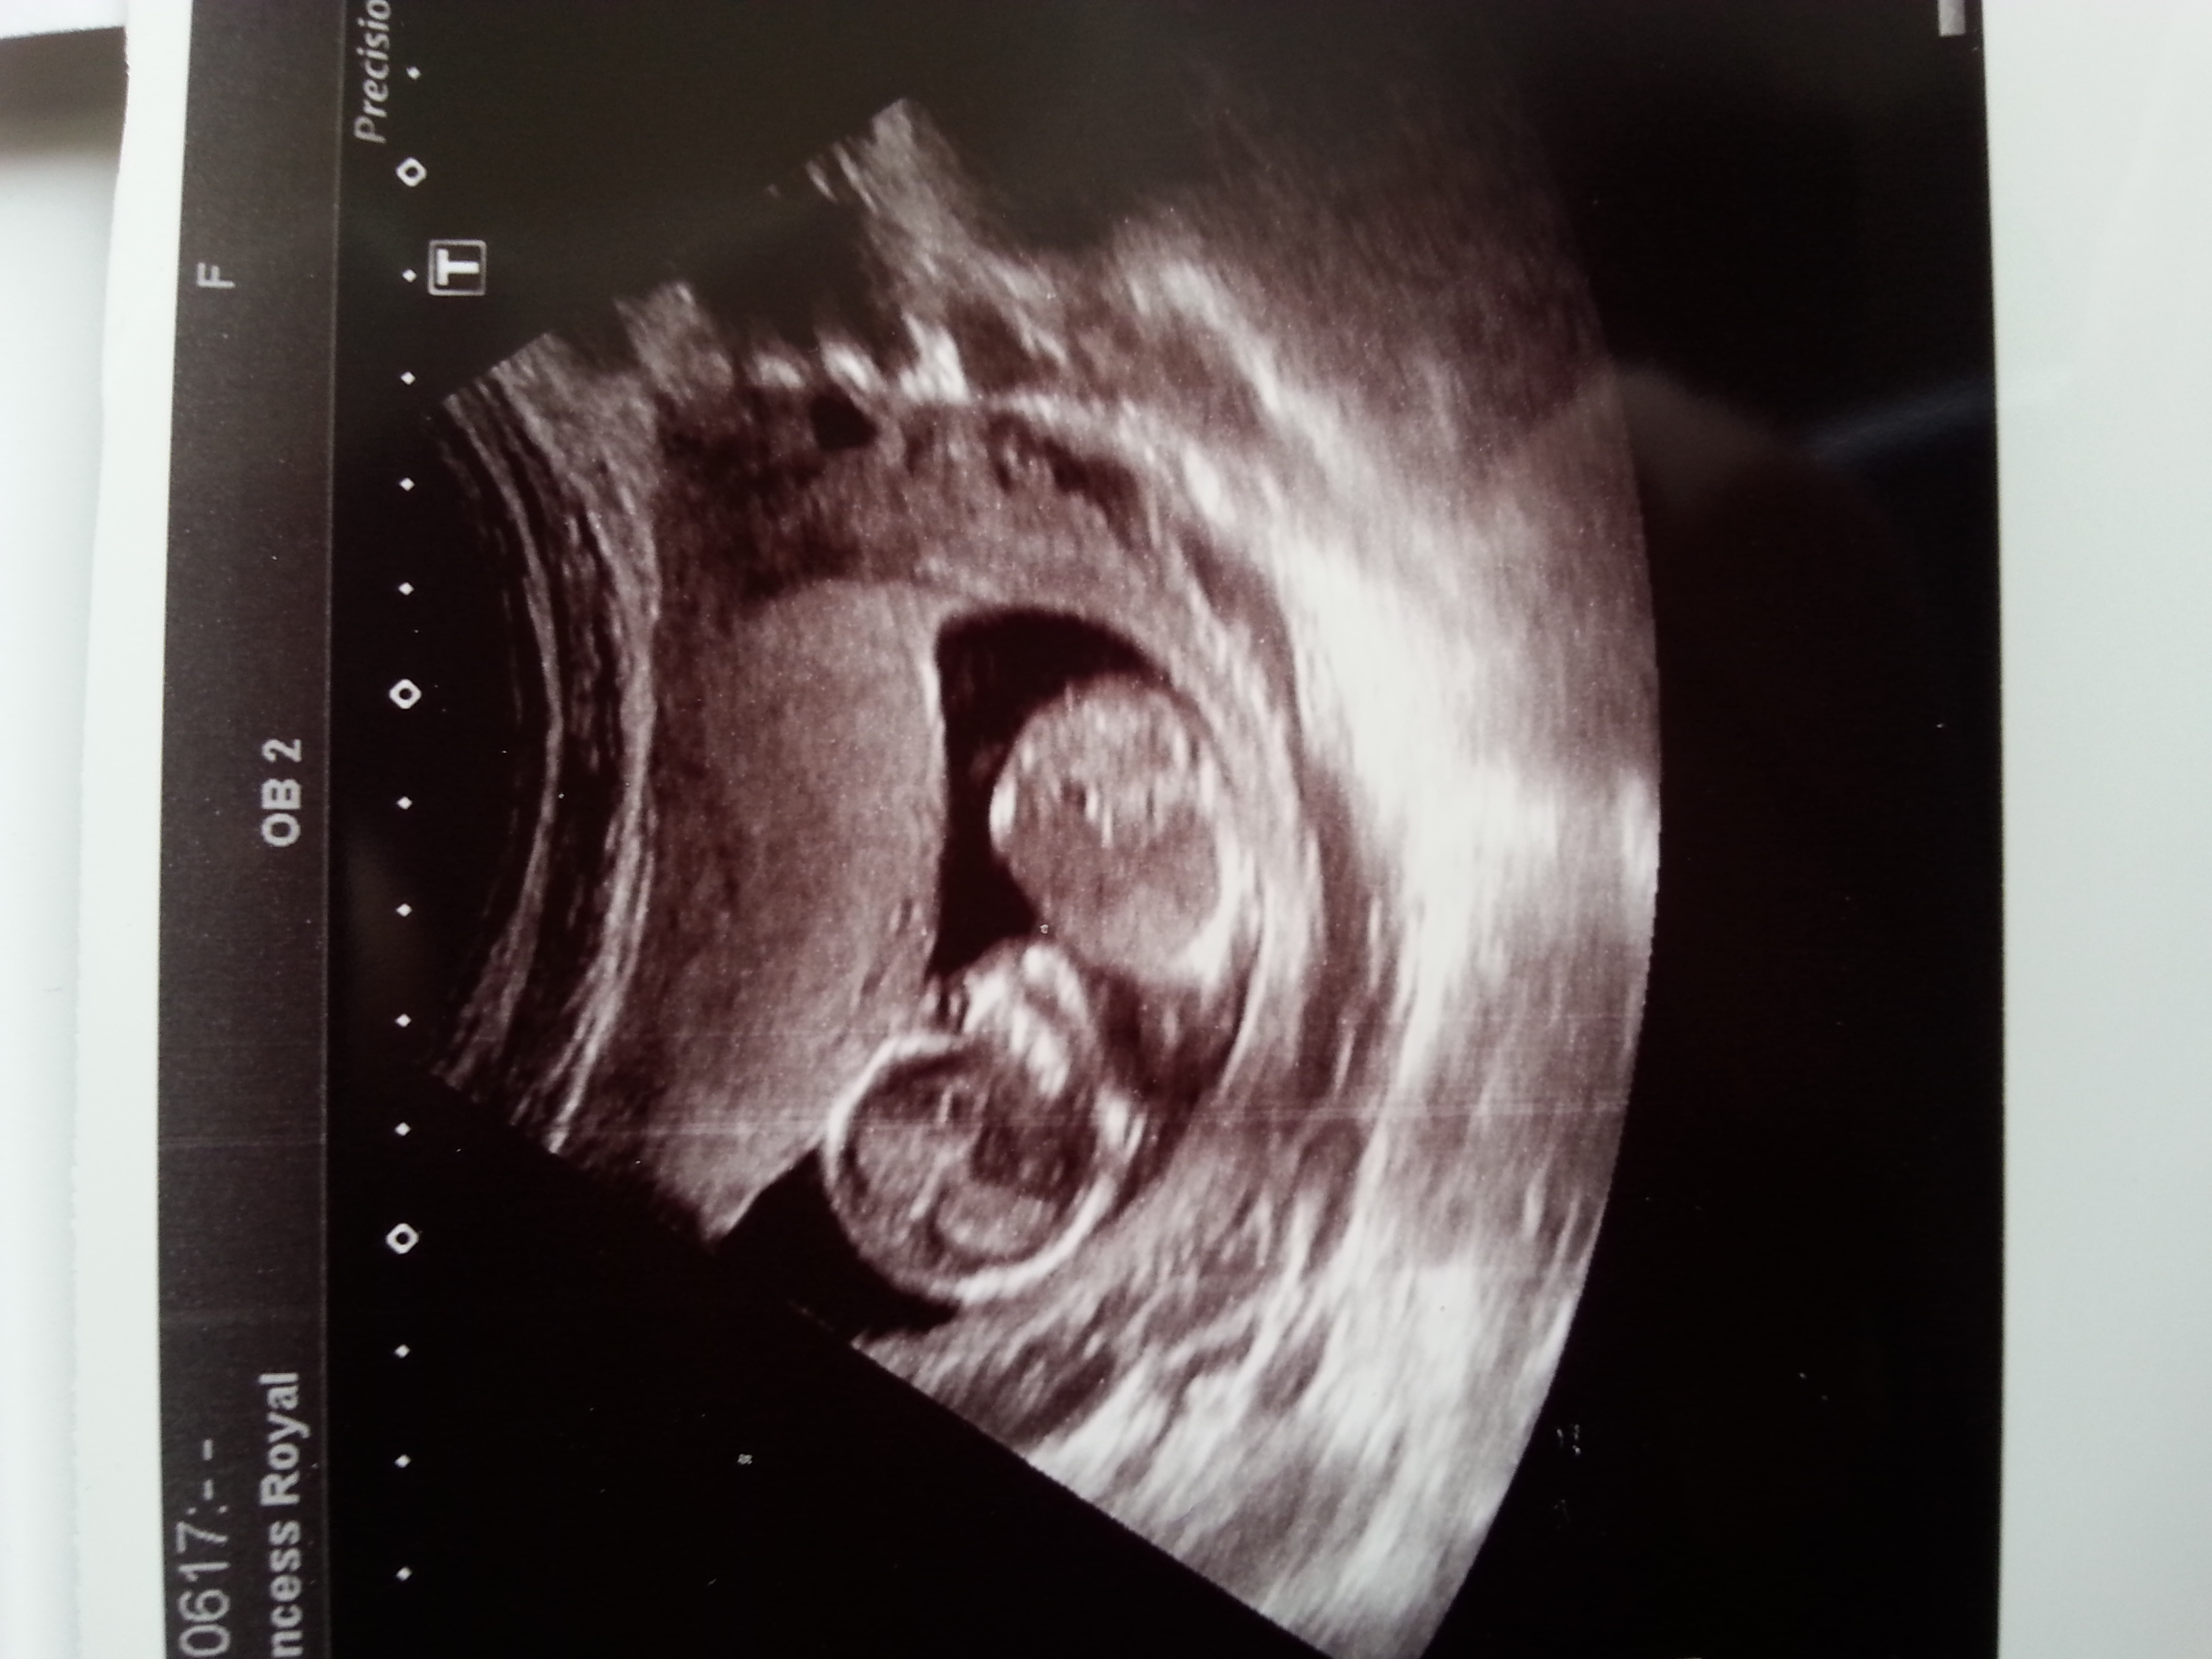

Gender guesses

Attachment 26866

Hello ladies, I had my nt scan today (baby was not cooperating so sadly no nub shot) but would anybody like to give me a guess? Based on vibes or skull? I know both those things are not reliable but its all in good fun :-) thank you.

If all in fun, I think I get a girly vibe from these. Not sure what from, though...

Yes all in fun :-) I didn't see anything at the baby's rump end which screamed boy at me so I'm still keeping my fingers crossed for a girl :-)

That little cuteness was not cooperating at all was it! It looks so snugly in there :)

No it wasn't lol it even turned its back on us a few times ha ha as if to say "no sorry I'm not in the mood to be measured today" lol. I really didn't expect to come away completely team green yesterday, I thought I would see something but no so I'm just taking away the fact that I didn't see anything which screamed boy at me so I still have hope for a girl, which I didn't have for my last pregnancy.